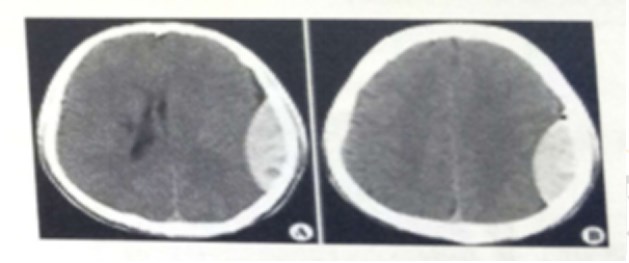

試題:男,44歲。頭部外傷12小時(shí)。結(jié)合CT片,此診斷為(2分)

A.硬膜下血腫

B.腦出血

C.硬膜外血腫

D.顱骨骨折

答案:C